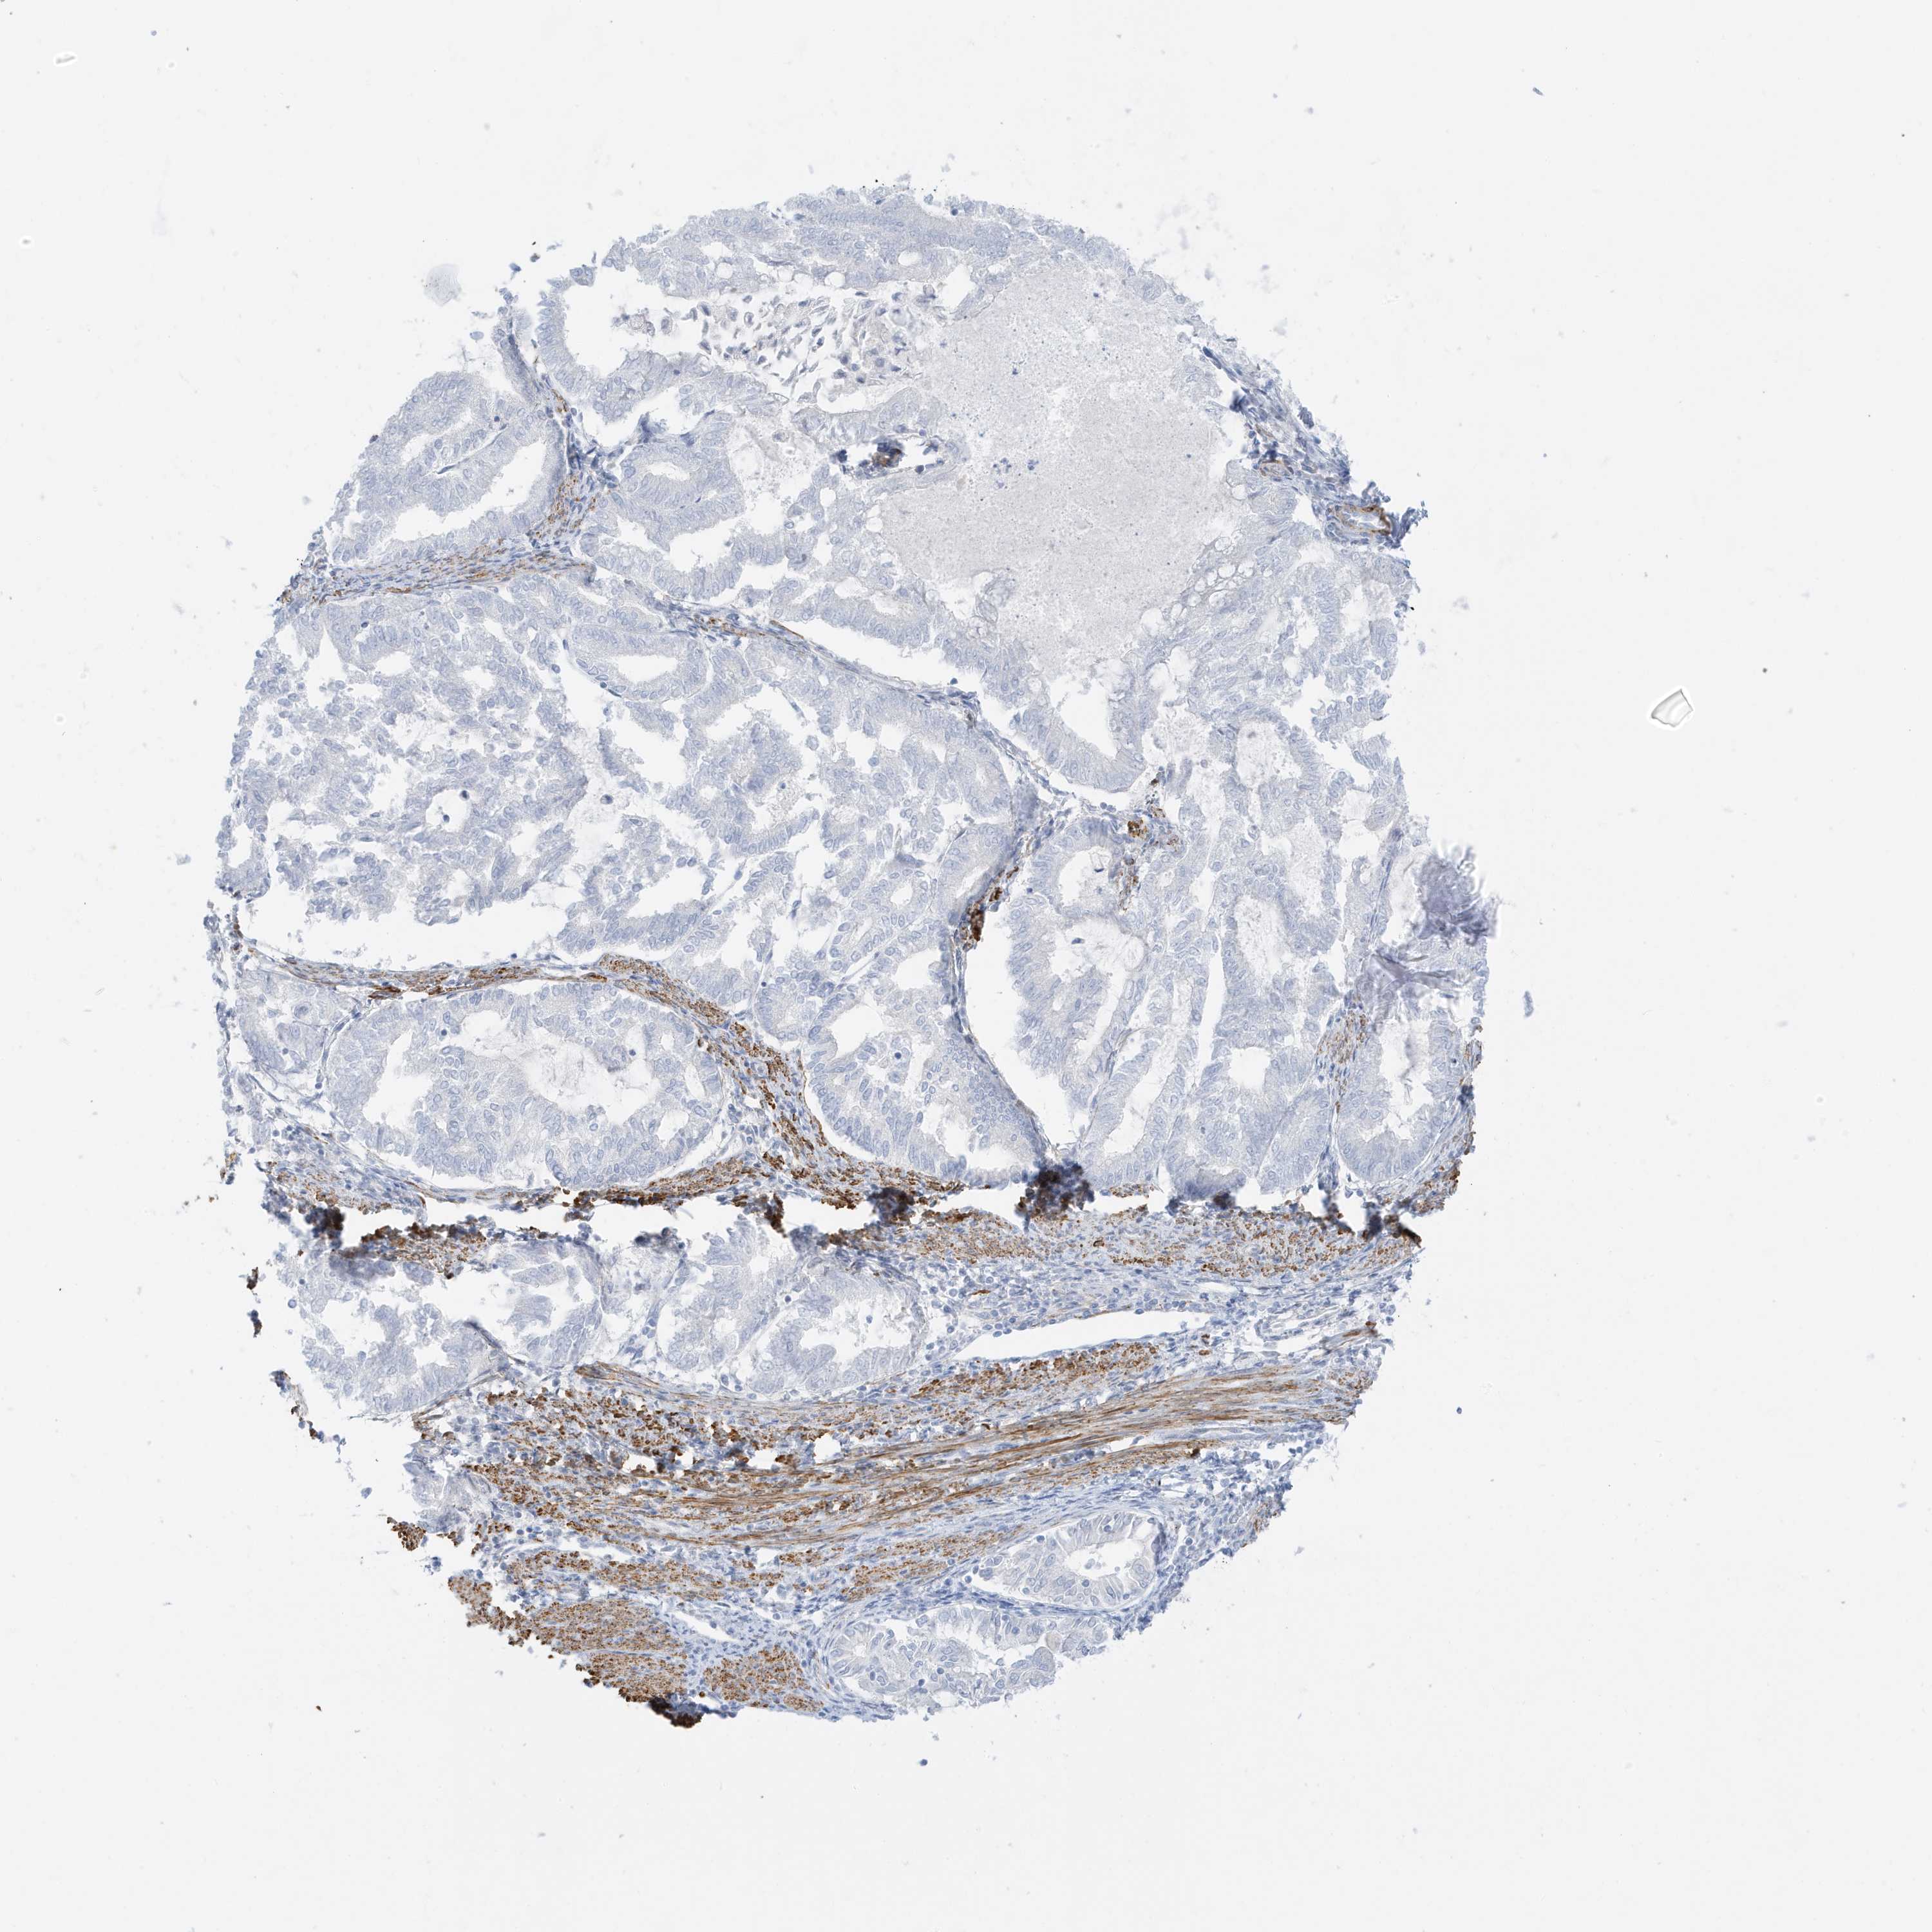

ENDOMETRIAL CANCER - Protein expressioni

A mouse-over function shows sample information and annotation data. Click on an image to view it in a full screen mode. Samples can be filtered based on level of antibody staining by selecting one or several of the following categories: high, medium, low and not detected. The assay and annotation is described here.

Note that samples used for immunohistochemistry by the Human Protein Atlas do not correspond to samples in the TCGA dataset.

Antibody stainingi

Antibody staining in the annotated cell types in the current human tissue is reported as not detected, low, medium, or high, based on conventional immunohistochemistry profiling in selected tissues. This score is based on the combination of the staining intensity and fraction of stained cells.

Each image is clickable and will lead to virtual microscopy that enables deeper exploration of all samples and also displays staining intensity scores, fraction scores and subcellular localization as well as patient and tissue information for each sample.

Antibody HPA035603

Antibody HPA035962

Staining

High

Medium

Low

Not detected

Intensity

Strong

Moderate

Weak

Negative

Quantity

>75%

75%-25%

<25%

None

Location

Nuclear

Cytoplasmic/membranous

Cytoplasmic/membranous,nuclear

Adenocarcinoma, NOS

Adenocarcinoma, metastatic, NOS